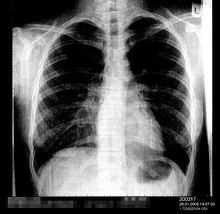

Lungenentzündung (hier ein Röntgenfoto

einer einseitigen Lungenentzündung) wird durch

Quecksilbervergiftung durch Quecksilberdampf

begünstigt |